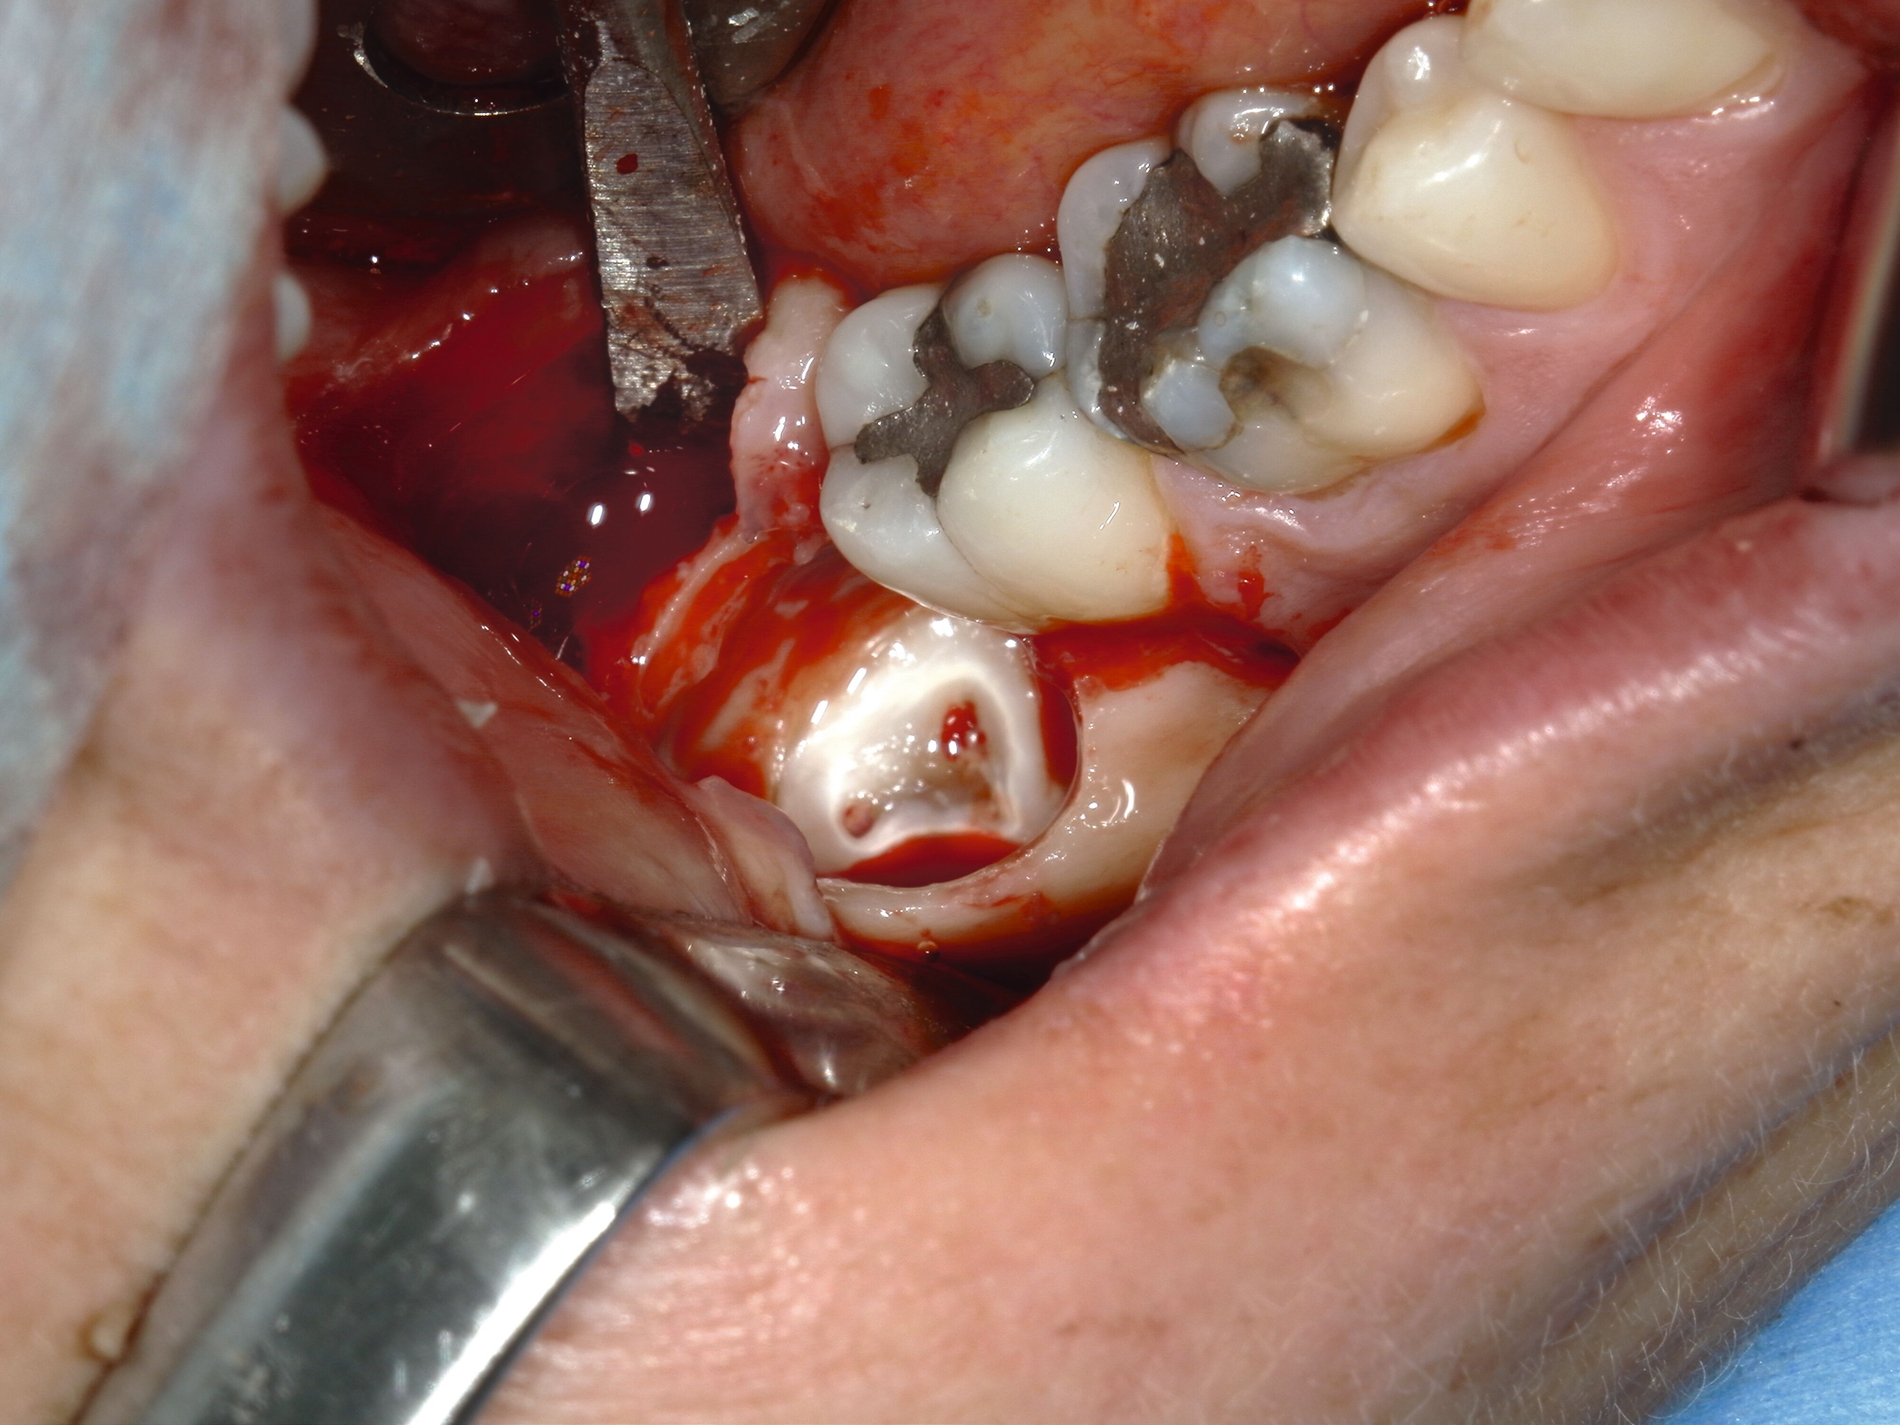

Nach Freilegung des Knochens kann ein Wundhaken nach Langenbeck eingesetzt werden sowie ein Bohr-Raspatorium zum Schutz des N. lingualis subperiostal lingual [Gutwald et al., 2019]. Unter Verwendung eines rotierenden Instruments (Kugel- und Lindemann-Fräse) oder Piezochirurgie wird der Knochen im Bereich der Zahnkrone abgetragen und diese freigelegt (Abbildung 8). Danach kann der Weisheitszahn vorsichtig mithilfe eines Bein‘schen Hebels anluxiert oder, falls dies noch nicht gelingt, mittels einer Lindemann-Fräse geteilt werden. Dabei wird am größten Kronendurchmesser die Krone mit der Fräse abgetrennt und die Wurzel anschließend separat entfernt (Abbildungen 9 und 10) [Gutwald et al., 2019; Schwenzer, 2019].

Nach Darstellung des Knochens kann der Weisheitszahn meist schon mit dem Hebel anluxiert oder mittels rotierendem Instrument freigelegt werden. Dabei muss möglichst oberhalb des Zahnäquators angesetzt werden, sonst kann der Zahn in die Kieferhöhle oder in das umliegende Weichgewebe luxieren. Anschließend erfolgen die Kürettage, die Entfernung des Zahnsäckchens, der Knochenkanten und des Granulationsgewebes sowie die Prüfung einer Mund-Antrum-Verbindung (MAV) mittels Bowman-Sonde. Bei positiver Testung erfolgt die plastische Deckung mittels Mukoperiostlappen oder bei ausgedehnteren Defekten mittels Bichat-Fettpfropf (Abbildungen 14 und 15) [Gutwald et al., 2019; Schwenzer, 2019].